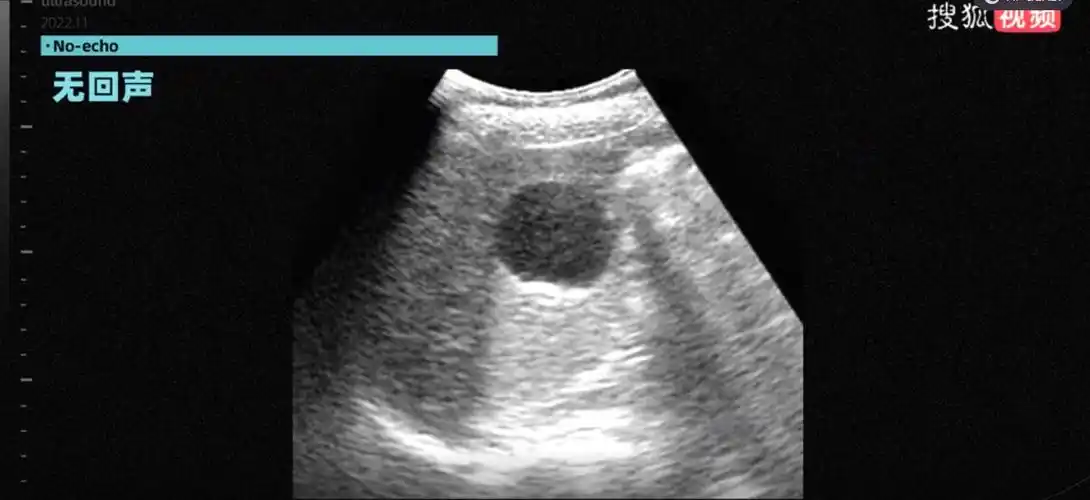

b超"回声"大揭秘:胆结石是怎么被发现的?_超声_图像_反射

患者胆囊穿孔伴胆囊周围包裹性积液,此时患者已出现明显腹膜炎症状,经